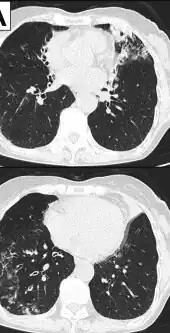

Image indicate bronchodilation, centrilobular granular shadow, and consolidation

- Pneumonia disease is also rare and appears in patients with some chronic pulmonary pathology. It usually presents as bilateral consolidating pneumonia, sometimes very severe.